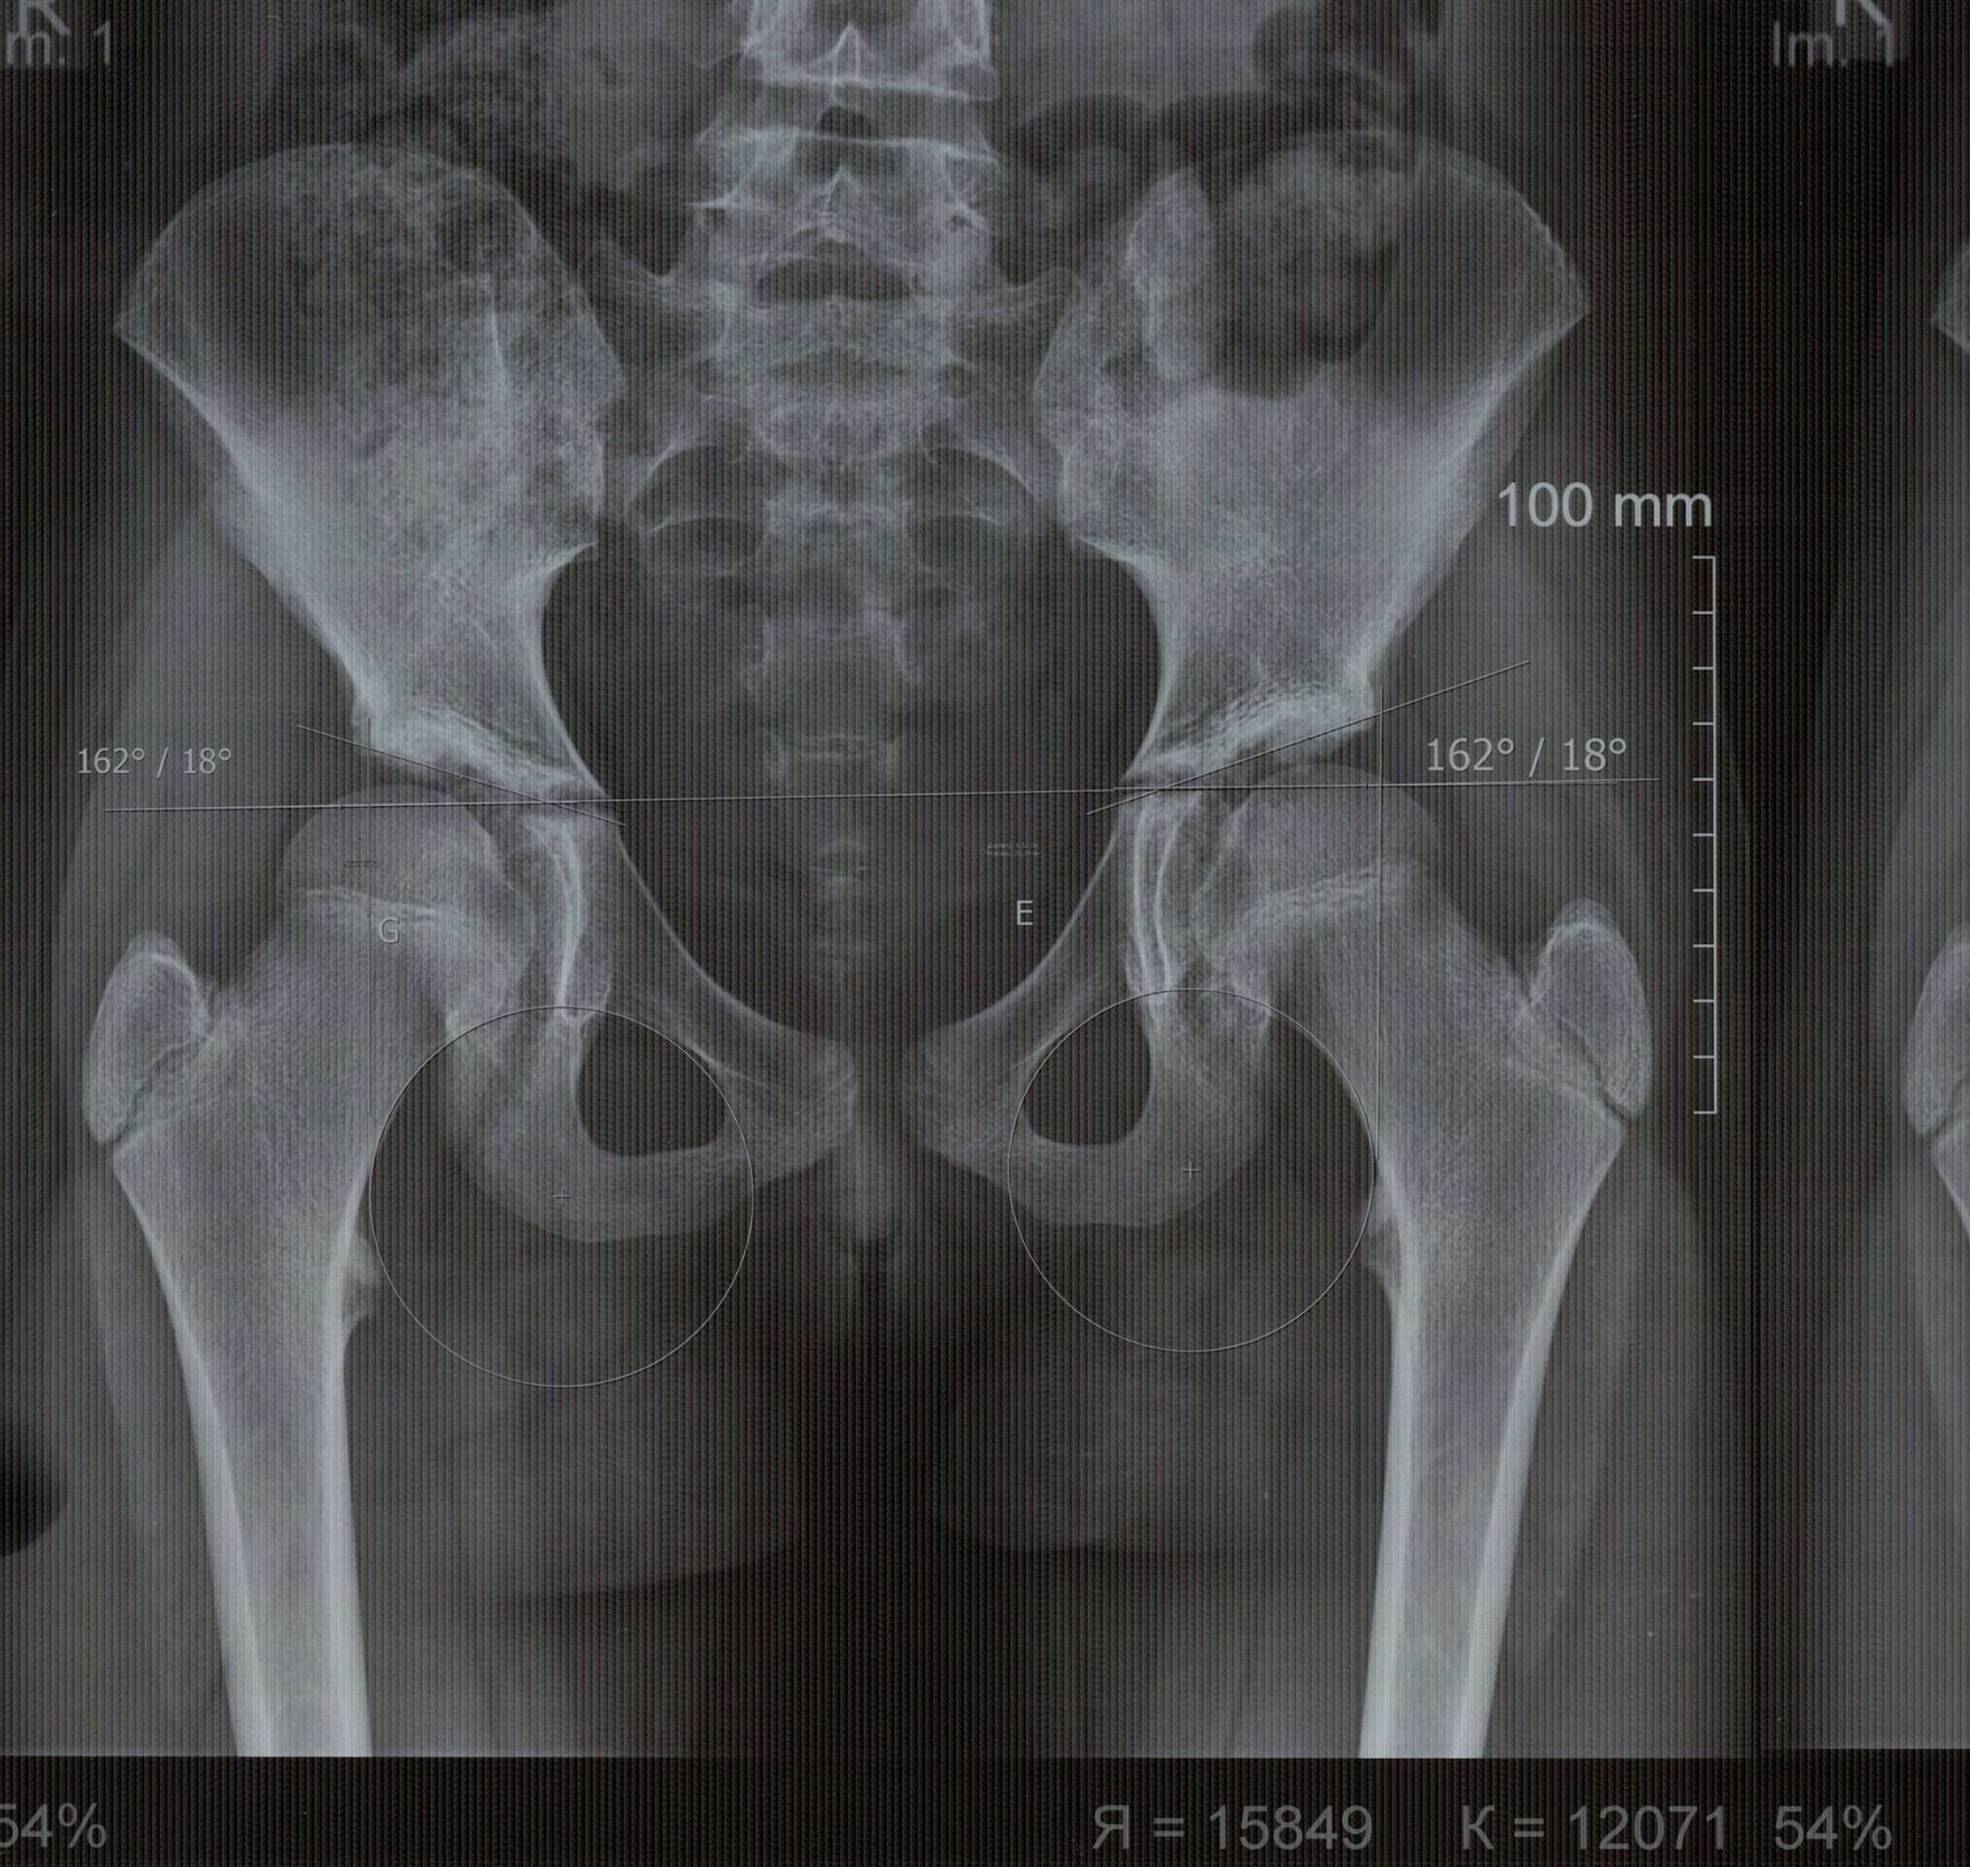

Рентген ТБС: Нормальные показатели

Раздел: Необычные решения